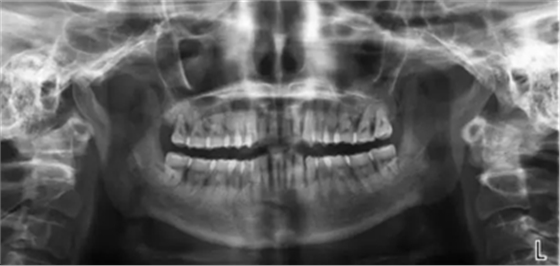

該患者本身就有慢性牙周炎,加上高血壓的基礎疾病,長期服用硝苯地平,這個是導致藥物性牙齦增生常見藥物之一,針對這樣的患者在牙周基礎治療時必要的,但在基礎治療的同時,一定要建議患者更改降壓藥物,同時必要時手術切除增生牙齦,可以達到很好的效果,見圖片(圖中白色為雙氧水沖洗后效果)。